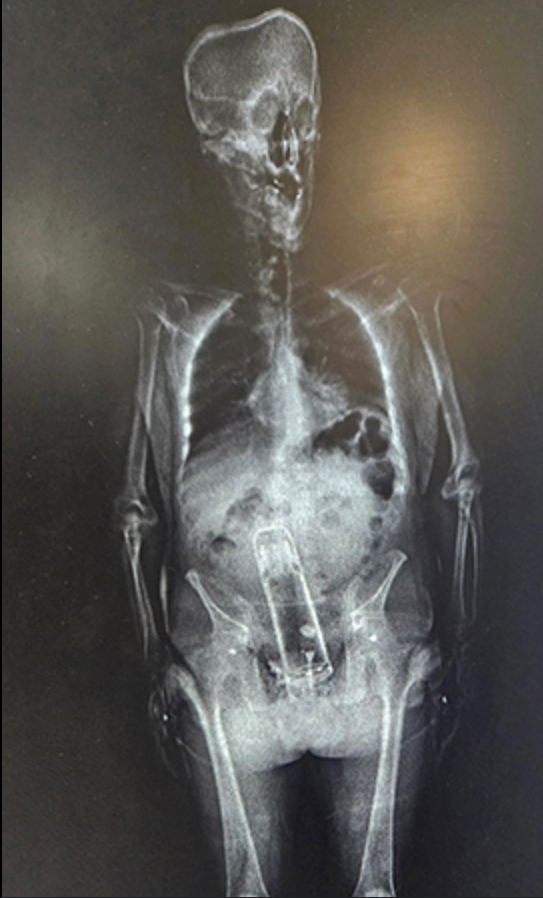

A garrafa térmica encontrada dentro do Frimier precisa de um ‘especialista’ para removê-la

A garrafa térmica encontrada dentro do Frimier precisa de um ‘especialista’ para removê-la (Gabinete do Xerife do Condado de Polak)

Segundo o Xerife, as autoridades foram obrigadas a levar Freimire para um local próximo Hospital Onde foi tratado por um “especialista” com ele.

“Foi uma provação e tanto, mas ele estava com uma garrafa térmica na prisão do condado hoje”, brincou o xerife. Ele acrescentou ainda que o jovem de 4 anos ameaçou matar o juiz para sua prisão, mas sua equipe provavelmente salvou a vida de Freimire.